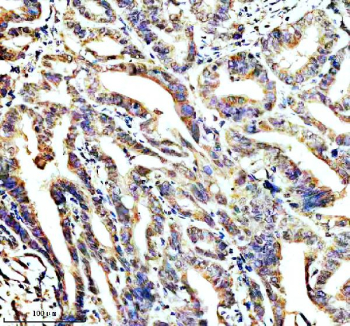

IHC staining of STOML2 using anti-STOML2 antibody. STOML2 was detected in a paraffin-embedded section of human colon cancer tissue. Heat mediated antigen retrieval was performed in EDTA buffer (pH 8.0, epitope retrieval solution). The tissue section was blocked with 10% goat serum. The tissue section was then incubated with 2 ug/ml rabbit anti-STOML2 antibody overnight at 4oC. Peroxidase Conjugated Goat Anti-rabbit IgG was used as secondary antibody and incubated for 30 minutes at 37oC. The tissue section was developed using an HRP secondary and DAB substrate.